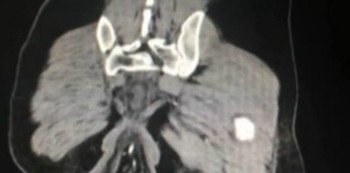

A CT scan revealed the 6.3-inch bulge hanging outside the patient’s anus, as well as blood spots and bruises along the patient’s intestinal wall.

• An x-ray, ultrasound, or CT scan may show problems with your child’s rectum. The healthcare provider may give contrast liquid to your child to help the intestines show up better in the pictures. Your healthcare provider may also place contrast liquid into your child’s anus. Tell the healthcare provider if your child has ever had an allergic reaction to contrast liquid.